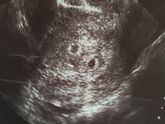

Больная тема для многих пузатых. У всех он проходит по разному. Кто-то и не замечает, Кто-то всю беременность тошнит. Расскажу про свой опыт.

Начиная с 7 недели меня мутило. Сильно. Я благодарила врача и свое начальство за то, что пошли навстречу и … Читать далее